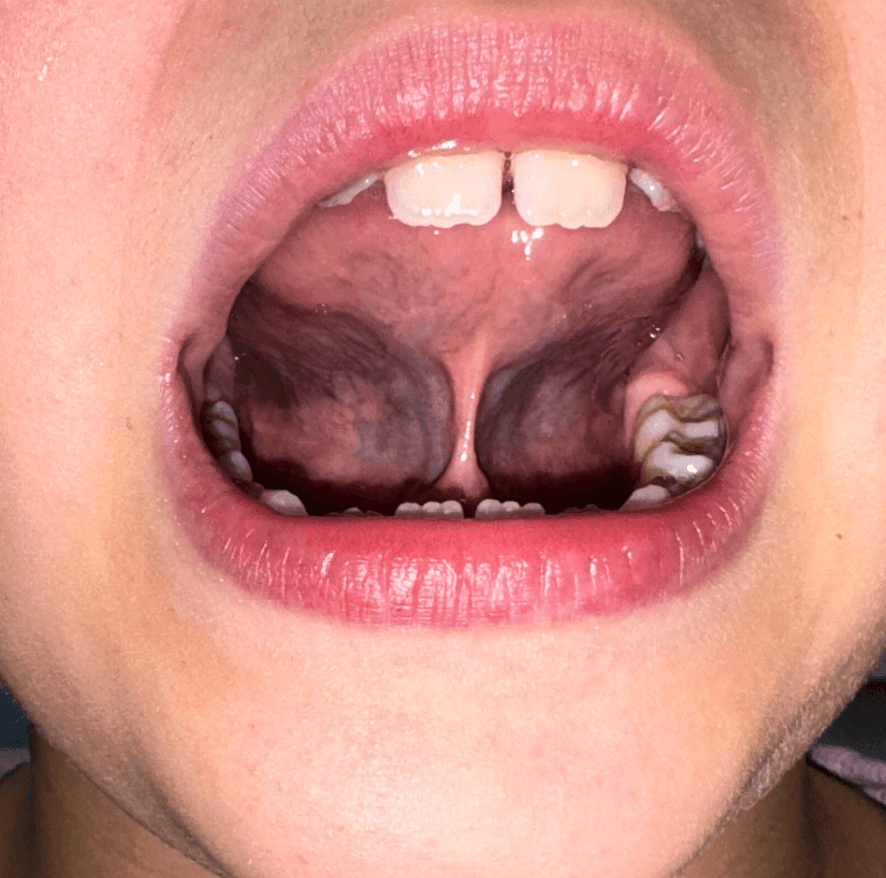

Przed: Język krótki, napięty, brak możliwości wypracowania prawidłowej pozycji spoczynkowej. Dno jamy ustnej sztywne, brak kontroli nad ruchomością języka.

Po: Elongacja mięśni języka, rozluźnienie dna jamy ustnej, język szeroko rozłożony na podniebieniu z prawidłowym kontaktem. Pacjentka utrzymuje pozycję bez wysiłku, bo ciało było przygotowane do funkcji.